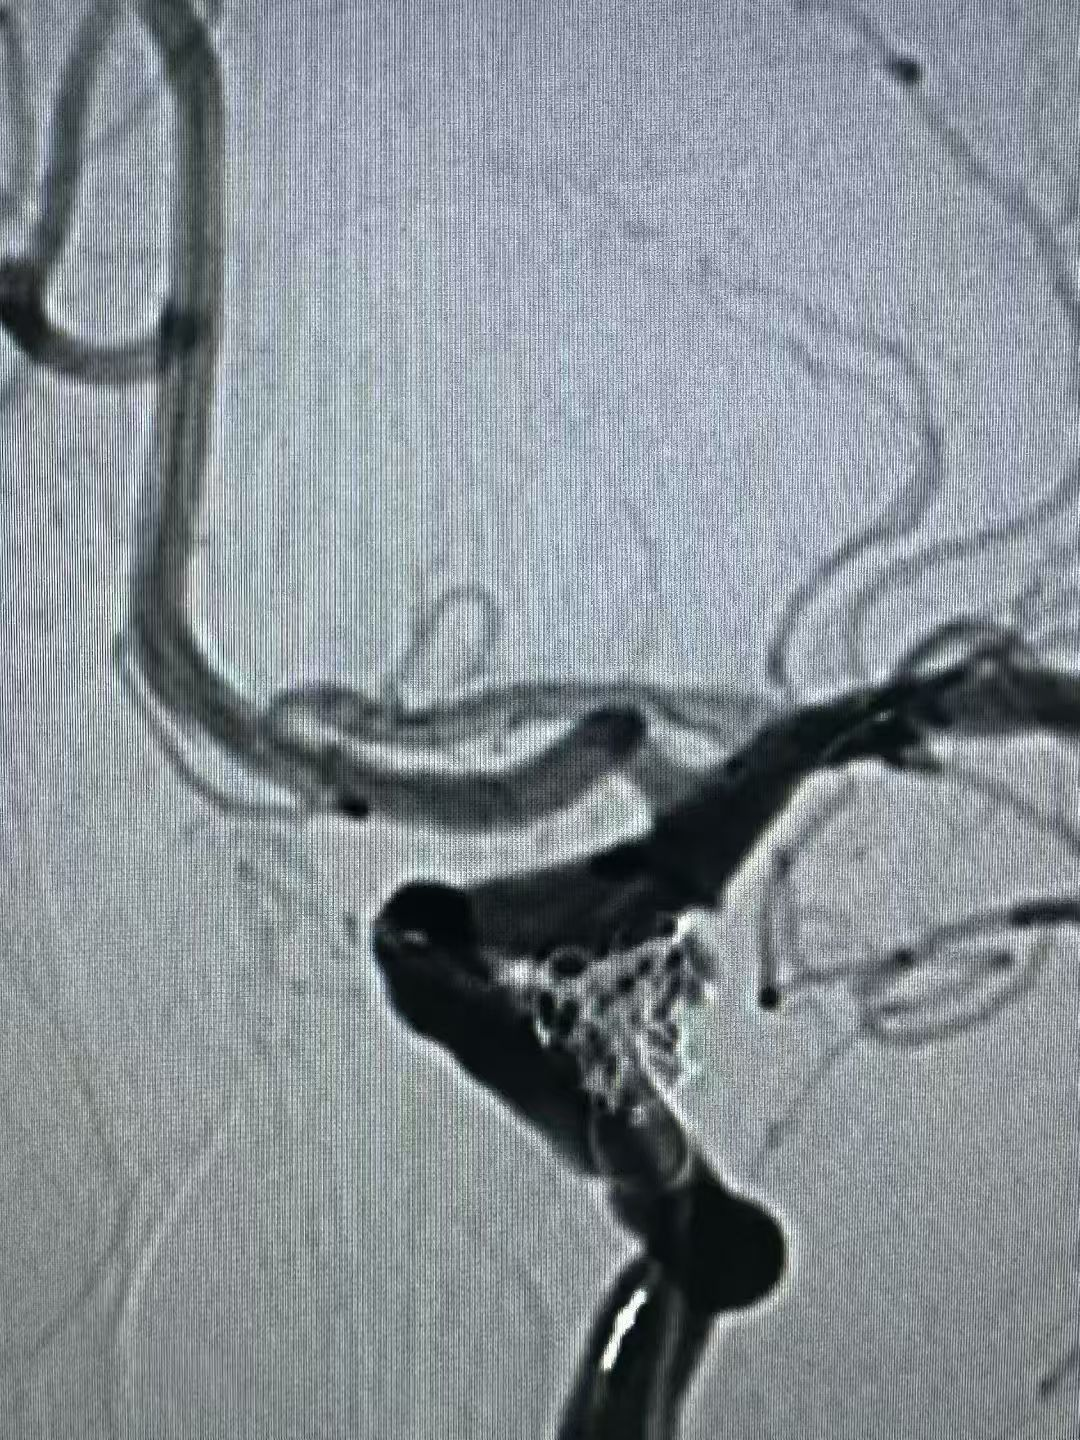

近日,桂平市中医医院脑病科介入团队成功为一例复杂颅内动脉瘤患者实施了微创介入手术。该手术采用了“弹簧圈联合血流导向密网装置”的先进技术,为患者解除了颅内“不定时炸弹”的威胁。此类高难度手术的成功开展,标志着我院在脑血管疾病的微创介入治疗领域具备了处理复杂病例的能力。 警惕隐匿的“脑内危机”:认识颅内动脉瘤 颅内动脉瘤并非肿瘤,而是颅内血管壁因局部薄弱而异常膨出的一个“小血泡”,其最大风险在于破裂出血。一旦破裂,致死致残率极高。临床上,动脉瘤在破裂前有时会因压迫邻近的神经而出现预警信号,如突发剧烈头痛、眼睑下垂、视物模糊等。 本例患者因“突发头痛伴左侧眼睑下垂”来院。经急诊脑血管造影(DSA)检查,确诊为左侧颈内动脉后交通段动脉瘤。该动脉瘤形态不规则、瘤颈宽大,治疗难度较高。若采用传统单一技术,可能面临诸多挑战。 微创介入:“双管齐下”的精准治疗策略 经过严谨的术前讨论评估,脑病科周辉主任团队为患者制定了“弹簧圈联合血流导向密网装置”的个体化手术方案。 与传统的开颅手术相比,该微创介入技术仅需通过大腿根部股动脉进行穿刺,利用一根极其精细的微导管,在数字减影血管造影机(DSA)的实时引导下,将装置精准输送至病变血管。手术团队首先将弹簧圈填入动脉瘤囊内,促进内部血栓形成;随后,将一张血流导向密网装置释放并覆盖于瘤颈开口处。该装置能有效引导血流主流远离动脉瘤,从而为动脉瘤的自然萎缩闭合创造条-件,显著降低远期复发风险。 在麻醉科、介入导管室的通力协作下,手术顺利完成。术后造影显示,动脉瘤栓塞效果满意,载瘤动脉通畅。患者术后恢复良好,次日即可下床活动,头痛症状缓解,神经功能得到改善。 学科进展:为复杂脑血管病患者提供更多选择 脑病科周辉主任介绍,“弹簧圈联合血流导向密网装置”技术是目前处理大型、巨大型、宽颈等复杂颅内动脉瘤的先进方案之一。这一技术的应用,拓展了微创介入治疗的适应范围,使得一些以往难以通过微创方式治疗或需行高风险开颅手术的患者有了新的选择。 健康提示:早筛早诊是关键 颅内动脉瘤多为隐匿发生。建议有高血压、高血脂、长期吸烟、有脑血管病家族史等高危人群,应重视脑血管健康筛查,做到早发现、早诊断、早治疗。切勿忽视突发性剧烈头痛、眼睑下垂等身体发出的“预警信号”。 桂平市中医医院脑病科始终致力于追踪和应用前沿技术,以专业的医疗团队和丰富的临床经验,为百姓的脑血管健康保驾护航。 健康咨询 健康咨询电话 0775—3384702 0775—3372569 门诊地址 桂平市中医医院 2号楼3楼366诊室 住院地址 桂平市中医医院 1号楼7楼、2号楼7楼 |